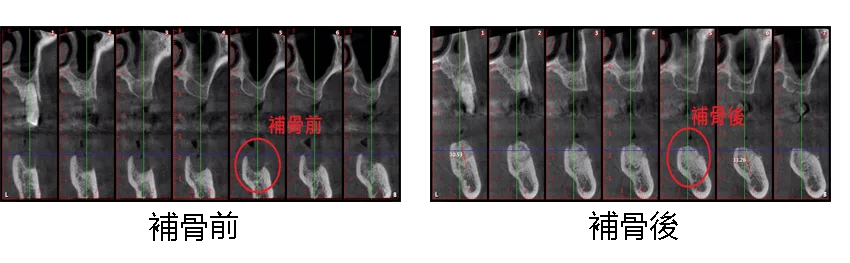

[ 湯先生植牙案例 ]